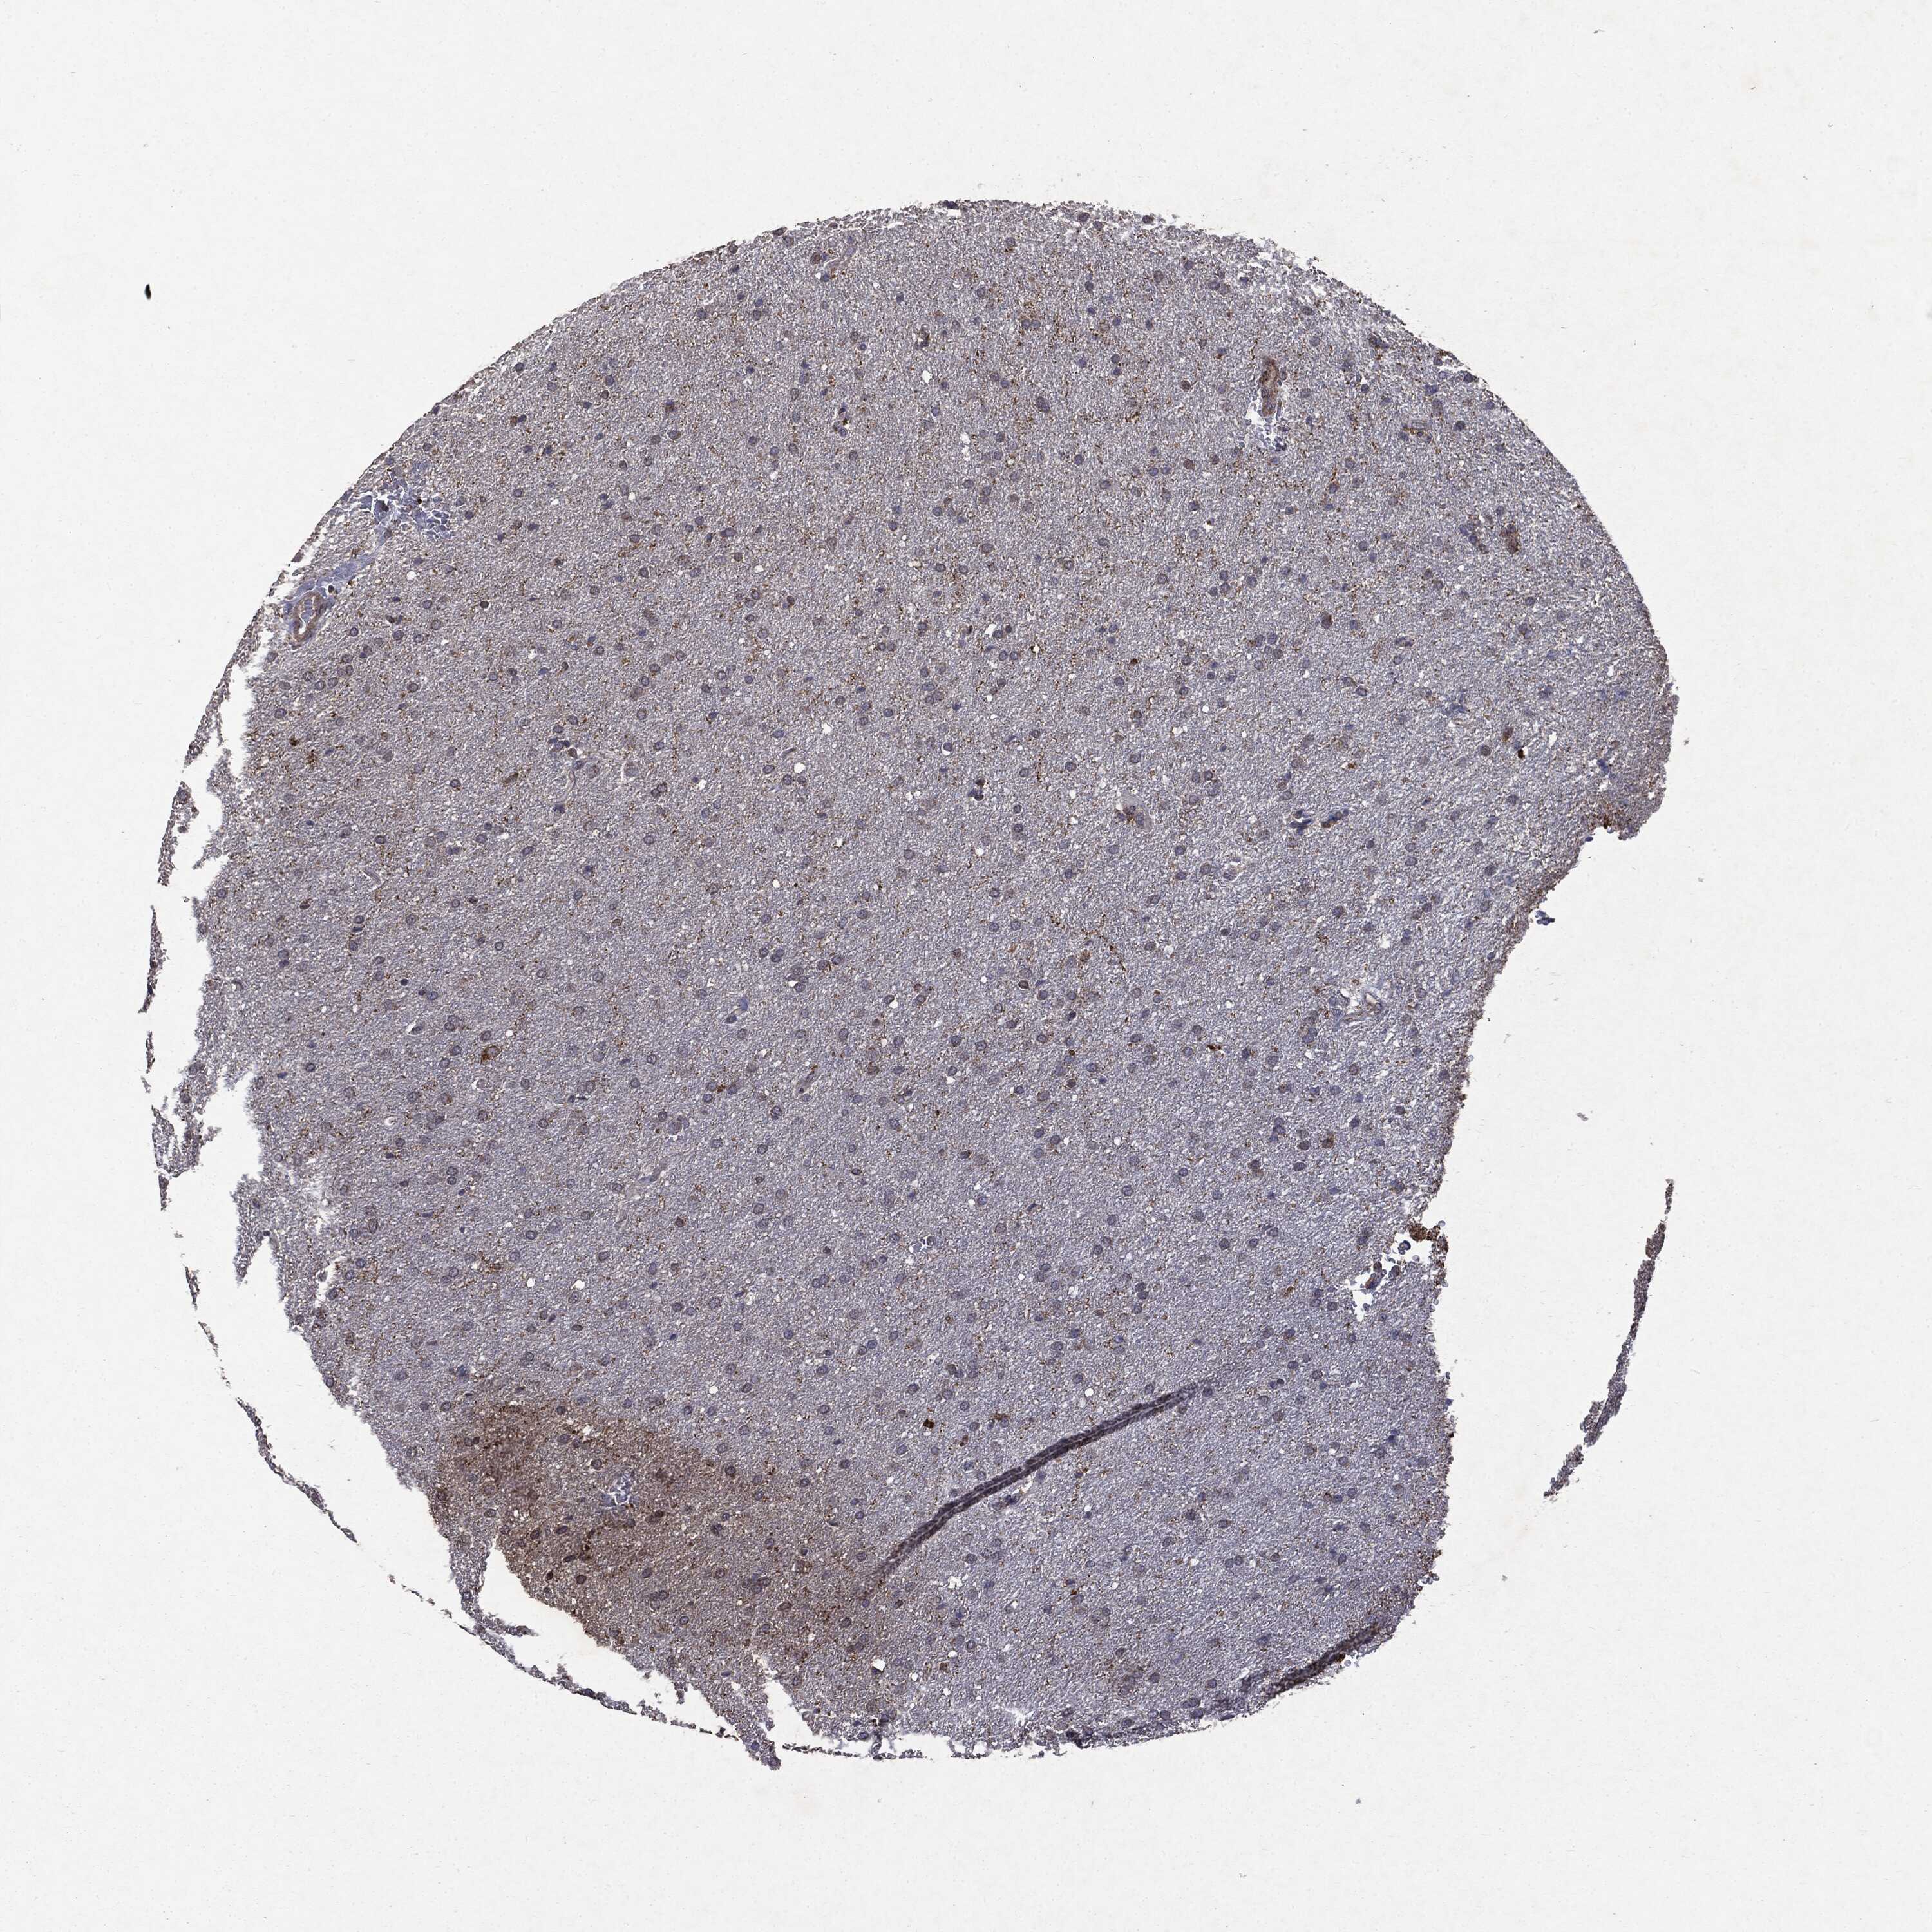

GLIOMA - Protein expressioni

A mouse-over function shows sample information and annotation data. Click on an image to view it in a full screen mode. Samples can be filtered based on level of antibody staining by selecting one or several of the following categories: high, medium, low and not detected. The assay and annotation is described here.

Note that samples used for immunohistochemistry by the Human Protein Atlas do not correspond to samples in the TCGA dataset.

Antibody stainingi

Antibody staining in the annotated cell types in the current human tissue is reported as not detected, low, medium, or high, based on conventional immunohistochemistry profiling in selected tissues. This score is based on the combination of the staining intensity and fraction of stained cells.

Each image is clickable and will lead to virtual microscopy that enables deeper exploration of all samples and also displays staining intensity scores, fraction scores and subcellular localization as well as patient and tissue information for each sample.

Antibody HPA031335

Antibody CAB004076

Antibody CAB080153

Antibody CAB080157

Glioma, malignant, Low grade

Glioma, malignant, High grade

Glioma, malignant, NOS